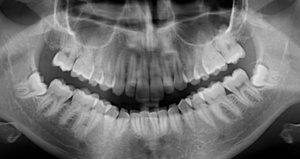

На протяжении трёх дней беспокоила несильная ноющая боль с правой стороны внизу. Сделали снимок, врач предположил, что боль возникает из-за зуба мудрости, который ещё не прорезался. И сразу записала на удаление.

Не знаю, можно ли что-то понять по приложенному снимку, но сколько примерно занимает удаление такого зуба и обязательно ли это?

Однозначно, причина беспокойств — это неправильно расположенная восьмёрка. Удаление необходимо, в противном случае мы получим скученность всего зубного ряда и потеряем седьмой зуб. Удаление сложное и требует профессионализма и опыта. Потребуется моя помощь — запишитесь к нам на приём к челюстно-лицевому хирургу.